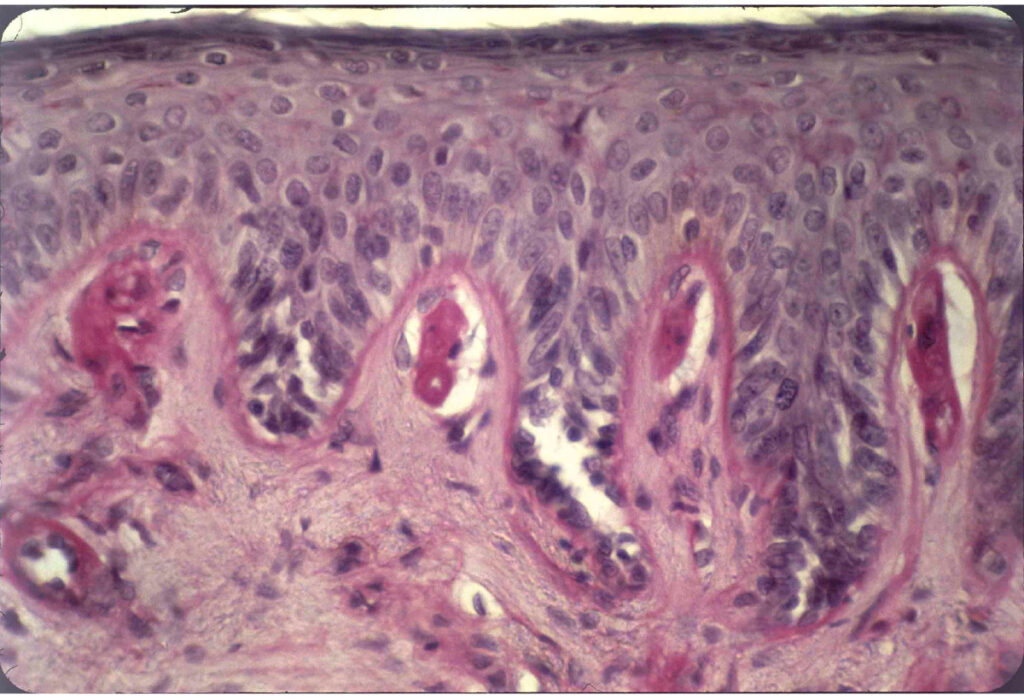

>>>Histopatologia

Histopatologia to dziedzina medycyny zajmująca się badaniem tkanek i komórek w celu diagnozowania chorób. W ramach tego badania, próbki tkankowe są pobierane z organizmu pacjenta, a następnie poddawane analizie mikroskopowej. Histopatolodzy oceniają zmiany morfologiczne w komórkach, co pozwala na identyfikację różnych schorzeń, w tym nowotworów, stanów zapalnych oraz innych patologii. Badania histopatologiczne są kluczowe w procesie diagnostycznym, ponieważ dostarczają informacji o charakterze i stopniu zaawansowania choroby. Analiza tkanek umożliwia także określenie odpowiednich metod leczenia. Histopatologia odgrywa istotną rolę w medycynie, gdyż pozwala na wczesne wykrycie wielu schorzeń, co zwiększa szanse na skuteczne leczenie. >>>